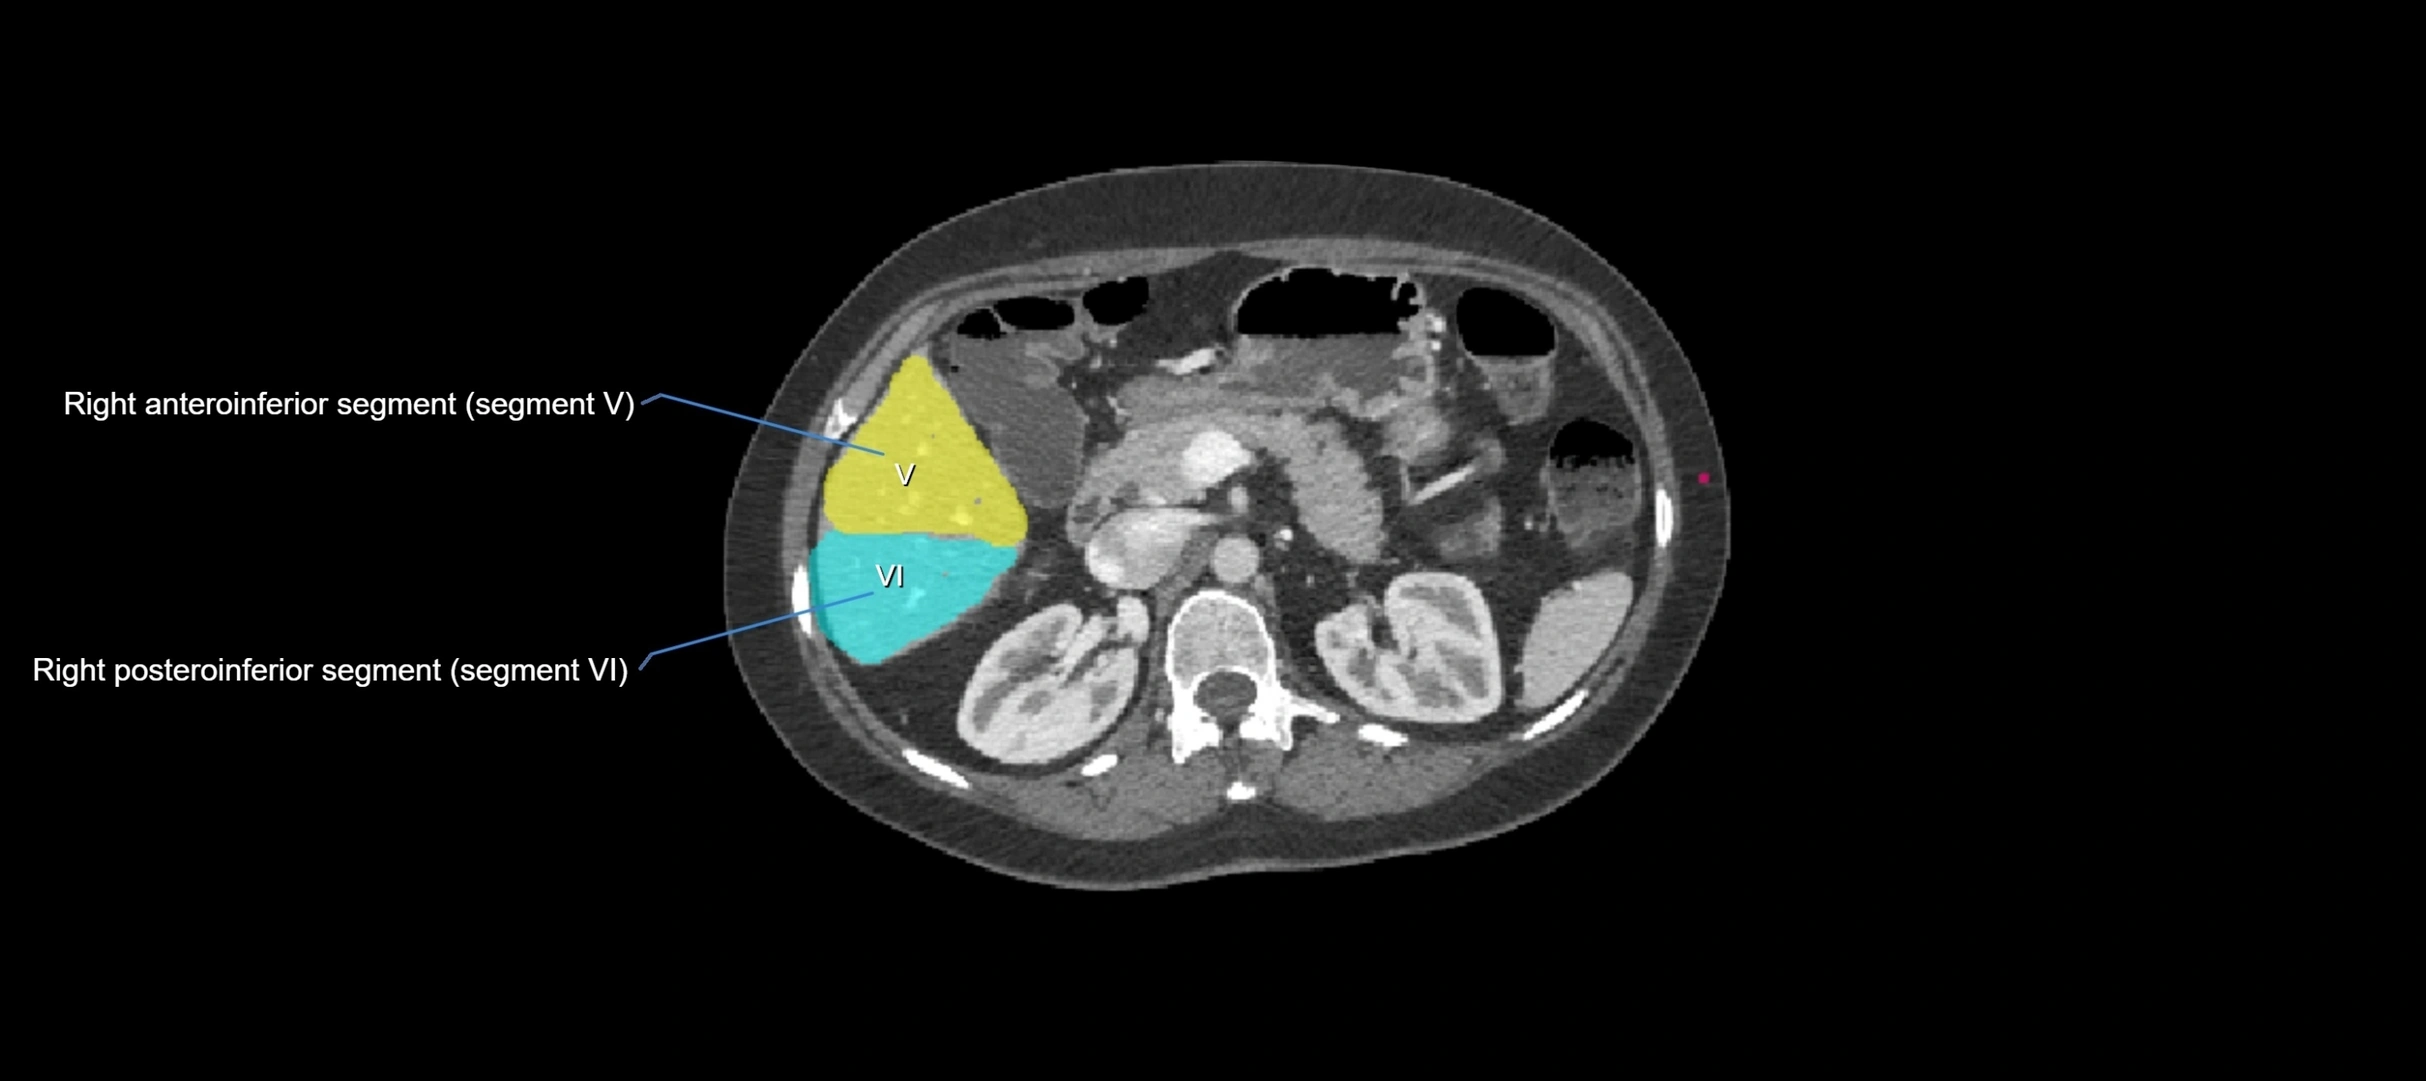

MRI image

image